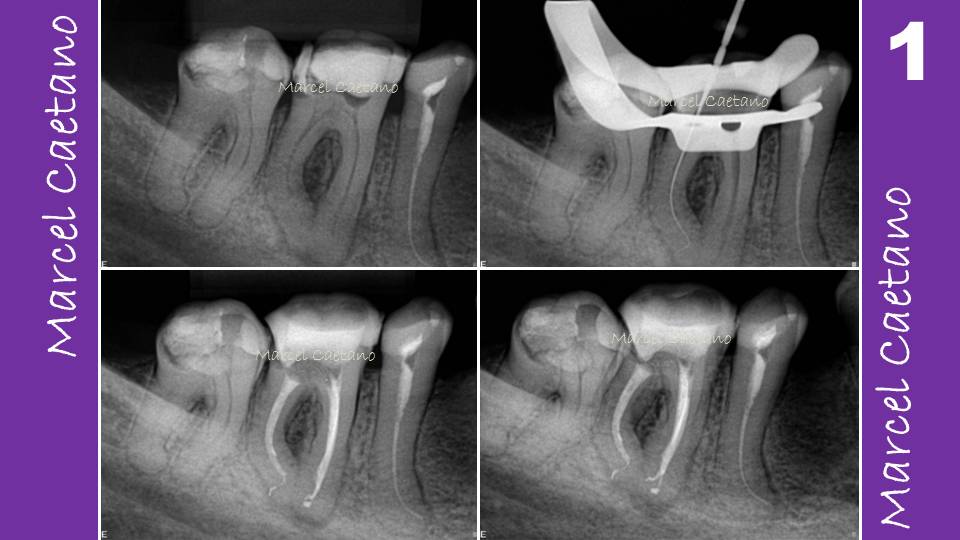

From endodontiaavancada.blogspot.com

Endodontia Avançada Um pouco sobre Anatomia do Canal, Forame Apical e Endodontic Apical Constriction It has been shown that 63% of the endodontic treatment failures are related to apical percolation due to an insufficient sealing [5]. The apical constriction (ac) was defined to be the narrowest area extending along a distance of 0.1 mm or more at the apex. Apical root canal complexities such as apical ramifications, apical constriction morphotypes, the ac to af. Endodontic Apical Constriction.